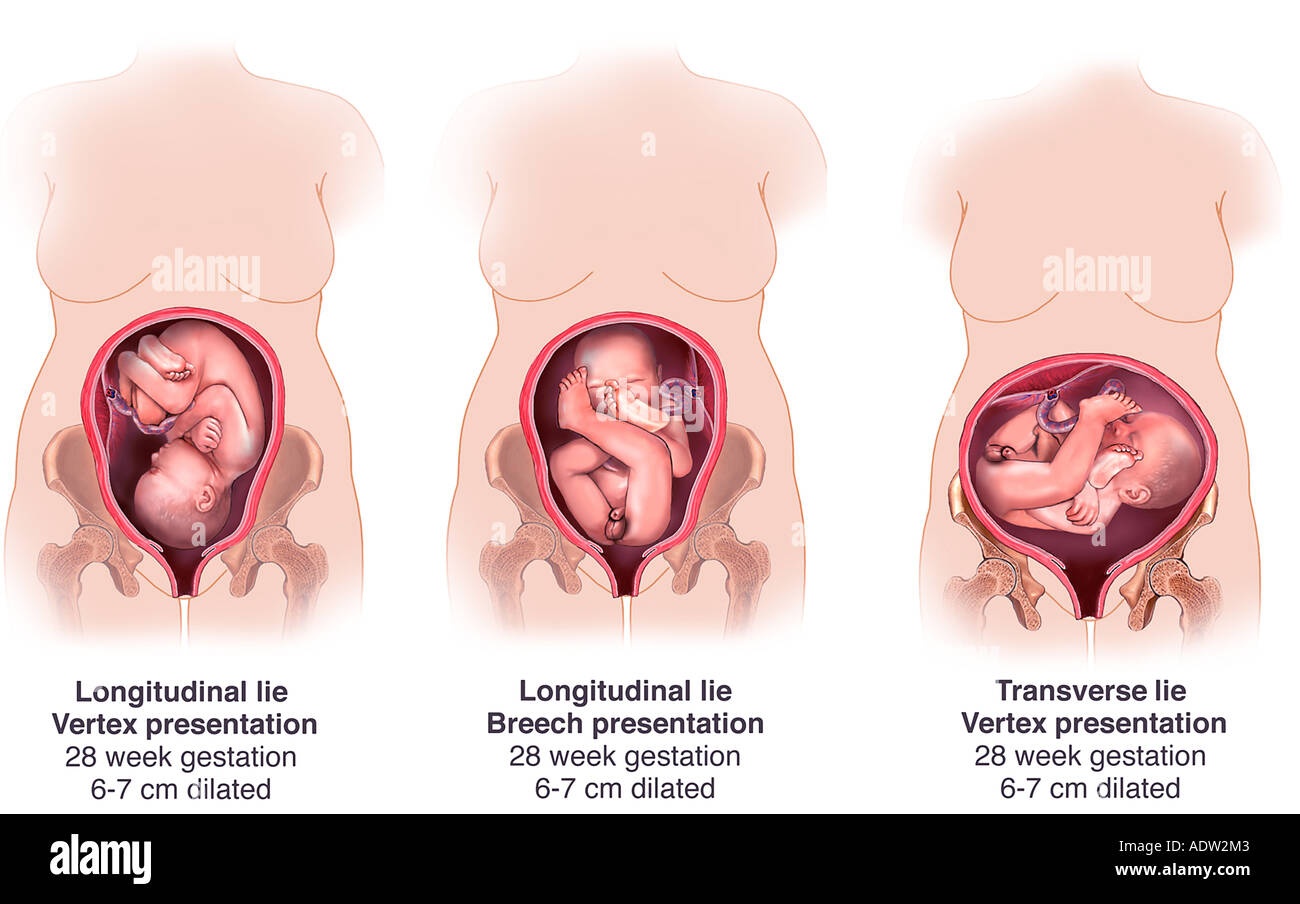

Плод 39 Недель Фото

Плод 39 Недель Фото 100 фото